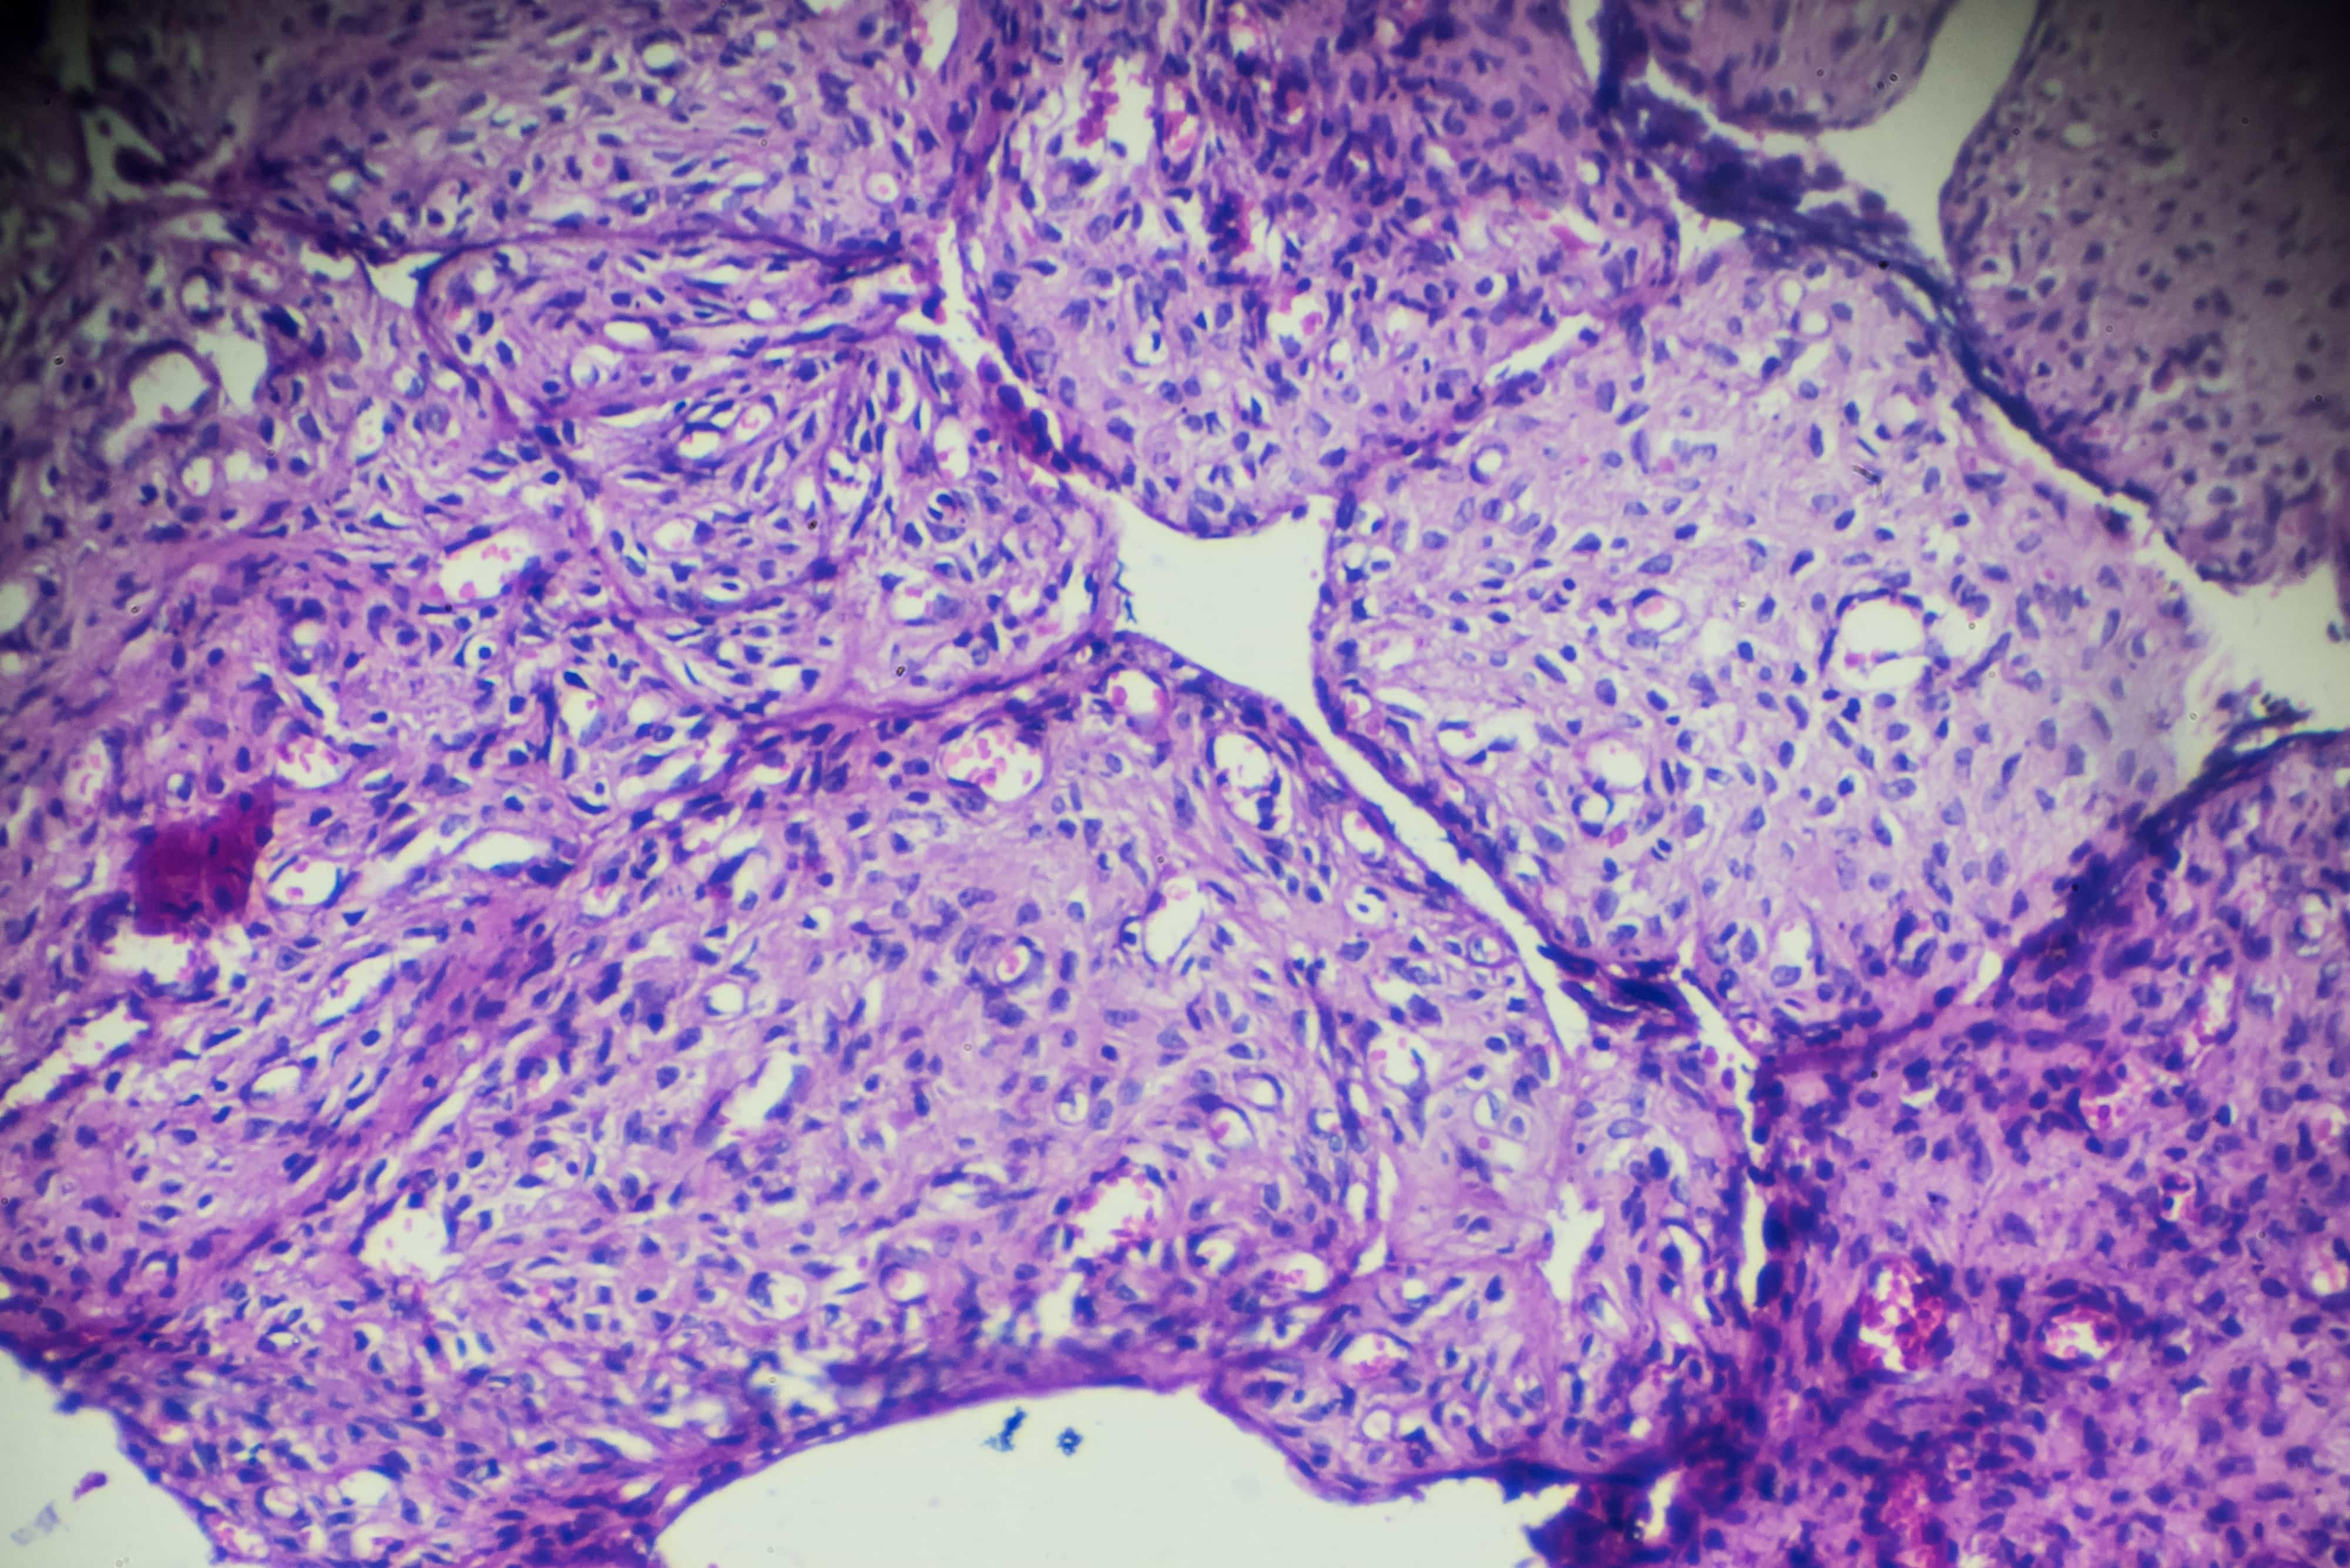

An international study led by Peter Mac has revealed the origin of mucinous ovarian cancer (MOC) confirming, unlike other types of ovarian cancer, this rare cancer is not seeded from elsewhere in the body.

The research provides new insights that could lead to a tailored treatment for MOC, which accounts for around 3% of all ovarian cancers. Importantly, the study found MOC is a true gynaecological cancer and not a distant metastasis of a cancer that started elsewhere - like the pancreas, bowel or breast.

The genetic events observed in MOC were compared to other tumours from many different tissue types, and this ultimately showed MOC as a unique cancer of the ovary. Benign and borderline mucinous ovarian tumours were also sequenced, revealing these were genetically related to MOC in a way that indicates MOC could have evolved from these less aggressive tumours.